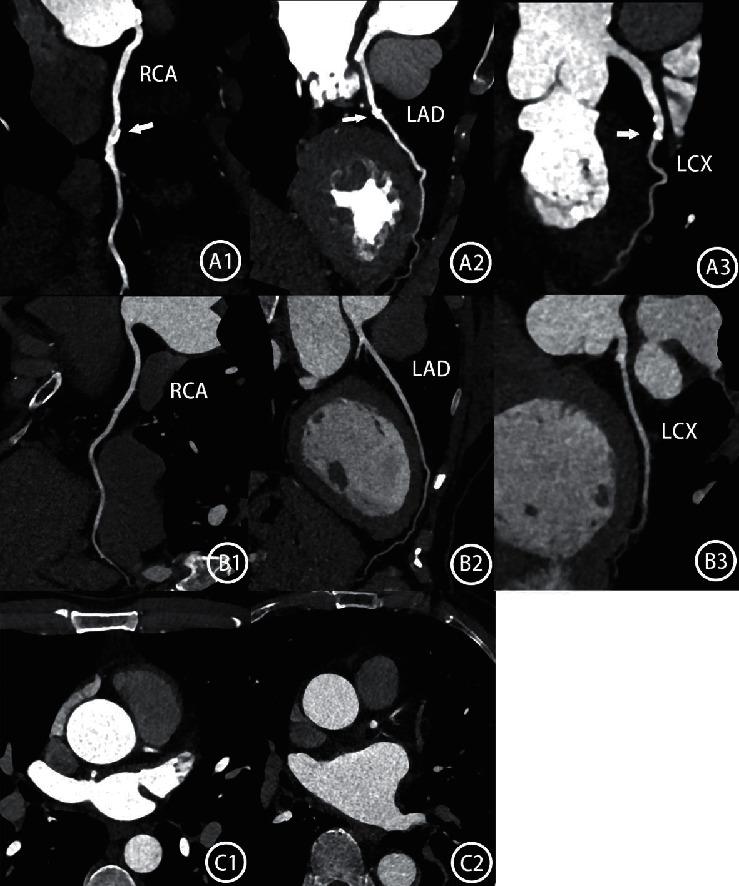

Ladder-Like Low Iodine Delivery Rate Injection Protocols Based on BMI at 70 KV by Automated Tube Voltage Selection in Coronary CTA.

To evaluate the feasibility of reducing the injection velocity and volume of contrast agent according to BMI, and the effect of body weight (BW), body surface area(BSA), body mass index(BMI),and blood volume (BV) on aortic contrast enhancement when the voltage of third-generation dual-source CT is selected at 70 KV.

A total of 280 patients selected at 70 KV were randomly divided into an experimental group and a control group. Each group was divided into 7 subgroups according to BMI ≤20, 20-21, 21-22, 22-23, 23-24, 24-25, and 25-26. The experimental group uses 2.3/2.4/2.5/2.6/2.7/2.8/2.9 ml/s injection speed with 350 mgI/ml contrast agents according to the subgroups; injection time was fixed at 10 s. In the control group, the fixed injection flow rate was 3.5 ml/s, time was 12 s with a total of 42 ml. Subjects in both groups were inspected to adaptive prospective ECG-gating sequence scanning, and subjective and objective image quality of the two groups were compared using Student's -test. BMI, BSA, and BV were calculated from the patient's body weight and height. We assess the relationship between aortic attenuation and BW, BMI, BV, and BSA using regression analysis or correlation analysis.

Significant differences exist in vascular enhancement between the two groups; SNR and CNR of objective image quality in the experimental group were lower than those in the control group ( < 0.05). Both groups had the same subjective image scores ( > 0.05). The number of vessels in the optimal enhancement range counts more in the experimental group than in the control group (2 value = 334.25,  < 0.05). In the control group, a weak to medium correlation was seen between vascular enhancement and BMI ( = -0.20), BW ( = -0.42), BSA ( = -0.46), and BV ( = -0.48) ( < 0.05 for all).

Compared to BW, BSA, and BV, a weaker negative correlation exists between vascular enhancement and BMI when ATVS selects 70 KV. However, as a much easier way to operate, the stepped low flow and low-contrast agent injection based on BMI was feasible, and the image quality was more homogenized than that of the control group.